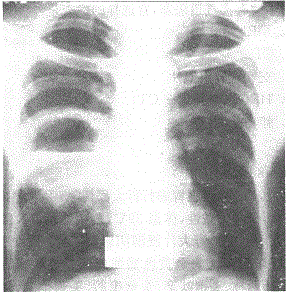

问题 阅读胸片 首先考虑的疾病是

选项 A.肺癌 B.肺结核 C.肺炎 D.肺脓肿 E.胸膜炎

答案 D